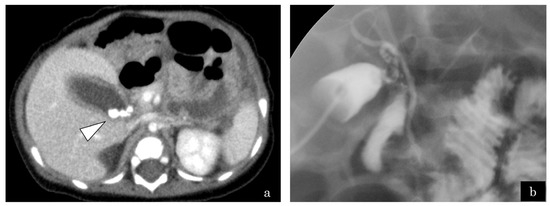

3.1.5. Case 5